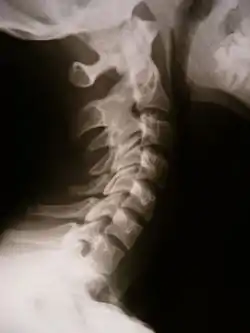

بههم چسبیدگی و جوش خوردن طبیعی یا غیرطبیعی در استخوان بهوسیله مواد استخوانی را پیوستهاستخوانی یا سینوستوز (Synostosis) میگویند.

![]() X-ray showing synostosis in the cervical spine | |

این پدیده میتواند یک پدیده طبیعی در سن بلوغ باشد مانند پیوستهاستخوانی سر استخوان یا غیرطبیعی باشد مانند اختلال در تشکیل استخوان (Dysostosis).